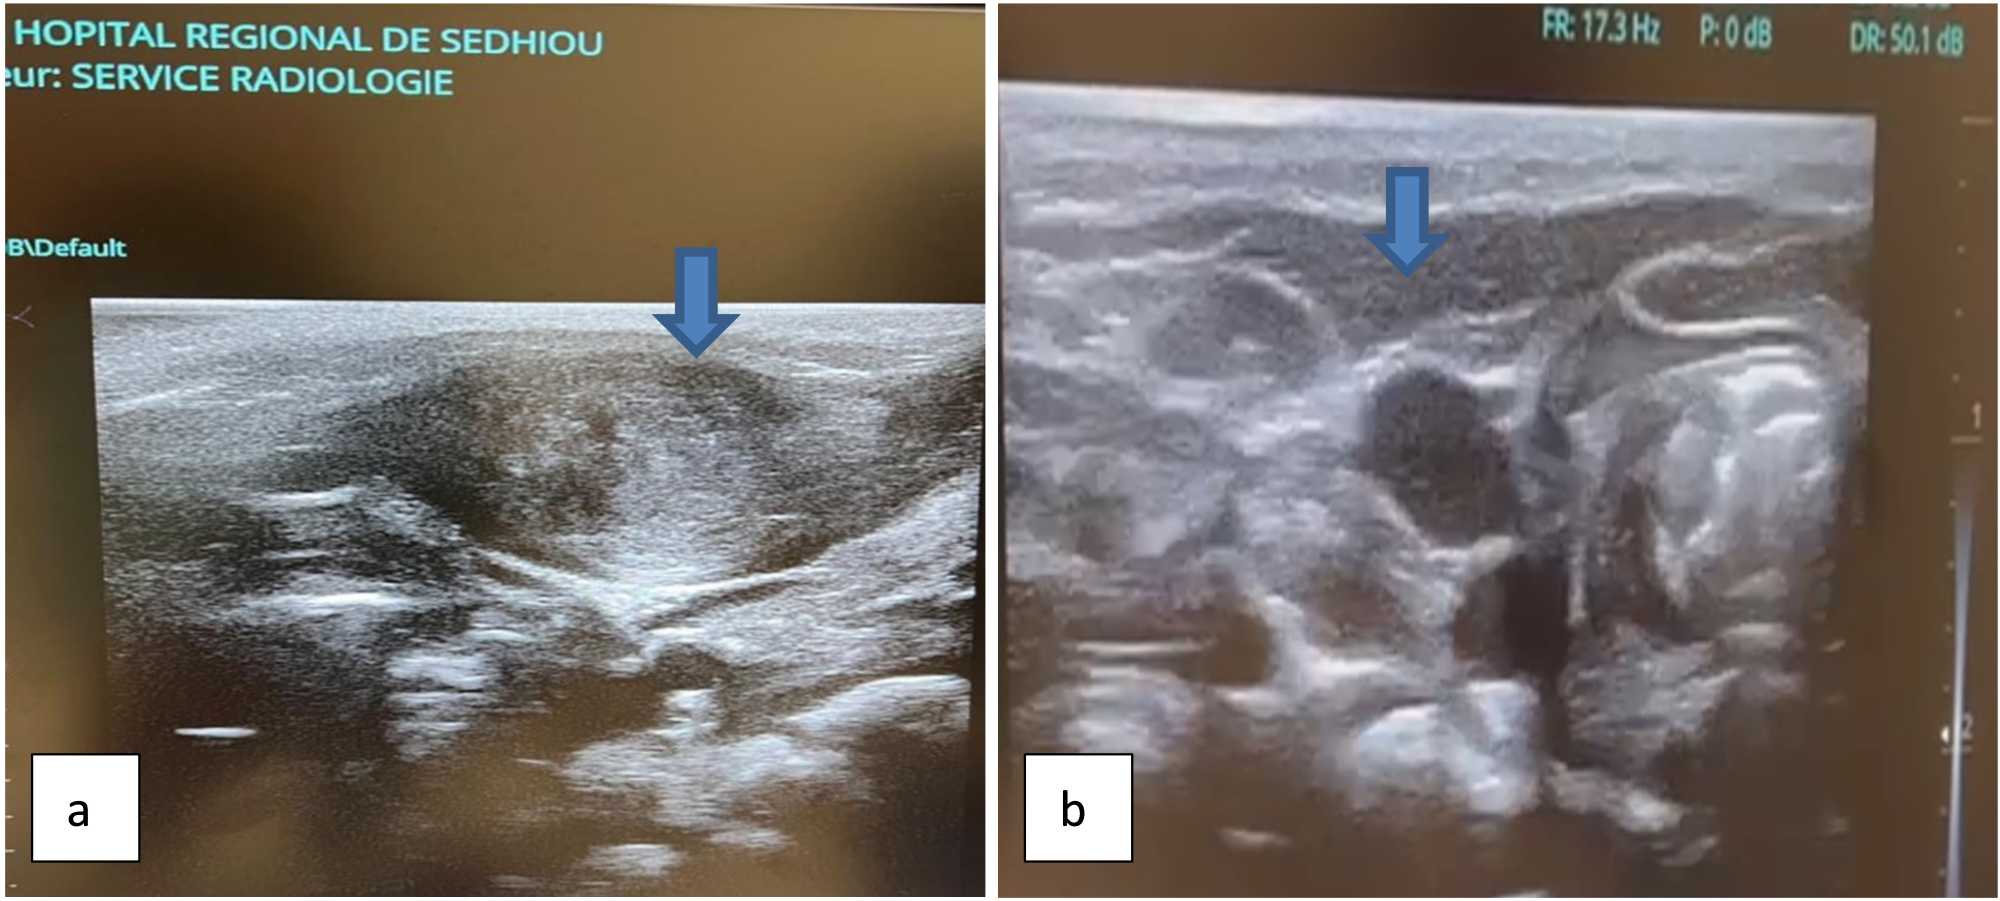

Figure 2. Longitudinal section (b) showing thickening of the SCM muscle compared with a normal muscle (a).

The patient was a one-month-old female infant who had been referred for an ENT consultation for a right laterocervical swelling that the mother had noticed 2 weeks after birth. The mother was primigest and primipare with intrauterine pregnancy without particularity. The delivery had occurred 36 weeks of amenorrhea by low way with episiotomy and the fetus presented itself by the seat. A concept of fetal suffering was reported: cyanosis, non-spontaneous cry, at birth. The child was revived and weighted 3.2 kg. No malformation has been objectified. The child’s general condition was satisfactory. Physical examination objectified a right laterocervical mass, painless of about 2 cm of large axis, mobile, developed at the expense of the Sterno-Cleido-Mastoid muscle (SCM) (Figure 1). The movements of the head were not limited but there was a tendency to rotate to the left. The lymph node areas were free. A cervical ultrasound had been carried out. This ultrasound (USG) clearly showed an oval formation with peripheral vascularization developed at the expense of the right SCM muscle, ISO echogenous compared to the muscle measuring approximately 26 × 10 mm (Figure 2). No significant modification of the internal vascularity has been observed. There was no cervical lymphadenopathy. Based on these clinical and ultrasound observations, the diagnosis of Colli fibromatosis was made. We have recommended physiotherapy at home as a processing method. Passive stretching of the SCM was recommended with contralateral inclination and ipsilateral rotation, three times a day for one month. We also advised the mother to wear the baby as often as possible on the back, her face turned towards the side of the tumor. We also explained to her that the procedure should not be forced and should be interrupted in the event of resistance.

The diagnosis is made when a firm, unilateral, laterocervical mass, mobile under the skin and at one with the sternocleidomastoid muscle, occurs in the first few weeks of life [4]. The rare bilateral symptomatology has been described by Kumar et al. in two cases [17]. A torticollis is often associated where its initial name as a congenital muscular tumor [21]. The SCM muscle plays a key role in the movements of the head. An attack by the tumor logically induces an imbalance of these movements. In our case, overall head movements were not restricted. However, the right SCM mass caused a subtle asymmetry in muscle tone, resulting in a mild tendency for the head to rotate to the left. This indicates partial fibrosis or stiffness of the muscle, which is insufficient to produce overt torticollis but can slightly influence head posture and rotation. Ultrasound remains the examination of choosing the diagnosis, with a sensitivity of 100% . Ultrasound allowed us, as for several authors, to easily diagnose pathology. The typical aspect is a fusiform thickening, well -limited heterogeneous of the sternocleidomastoid muscle on the affected side, there is no vascular and lymphatic involvement [22] [23]. Ultrasound eliminates not only the other critical lesions cervical such as gill cysts and thyreogloss cysts but also inflammatory lesions such as lymph node tuberculosis and the neoplastic conditions which could be non-malignant (hemangioma, cystic hygrome) or malignant (neuroblastoma, Rhabdomyosarcoma, and lymphoma) [11]. Other radiological examinations such as computed tomography (TDM), magnetic resonance (MRI) imagery can intervene in the diagnosis of lesion. At CT, the muscle appears extended, Isodense. At MRI, there is a decrease in the T2 mass signal compared to the signal in T1, linked to the presence of fibrous tissue. However, these methods expose infants to ionizing radiation [24]. Cytopunction can take place in the diagnosis of pathology. It highlights fibroblastic proliferation, muscle atrophy, giant muscle cells and an absence of inflammatory cells. Several studies show the prominent place of cytopunction in the diagnosis of the tumor [19] [20] [25]. Although cytopunction is a non-invasive technique, it can be either expensive or not available in certain hospitals as is the case in our hospital establishment.